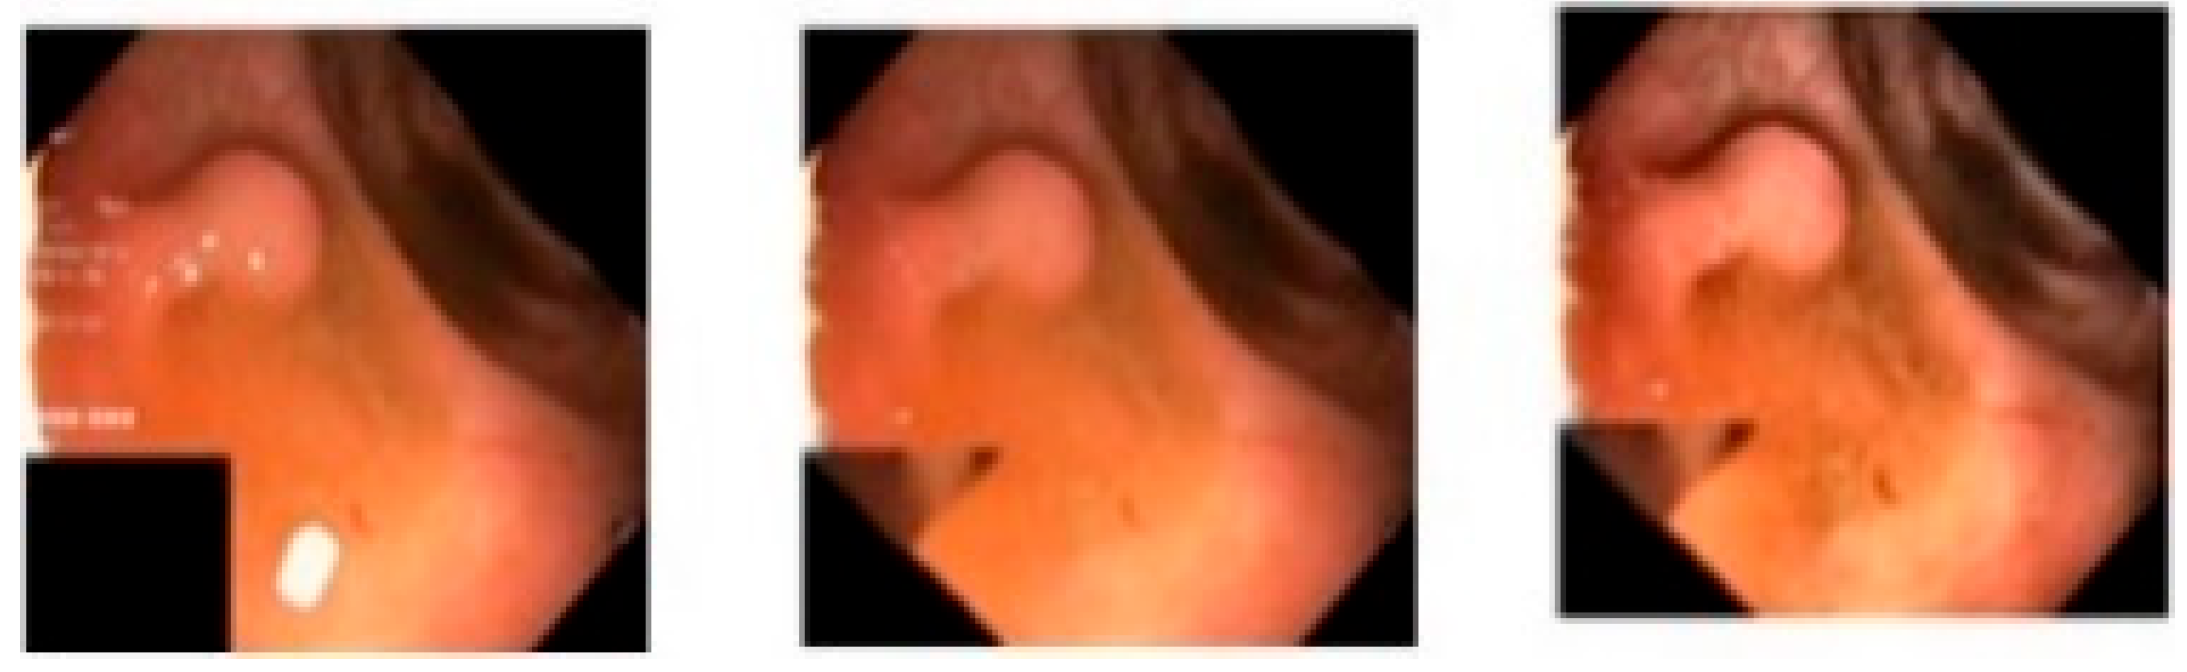

The main challenge in the case of region-of-interest extraction in polyps is that the number, size, and shape of polyps vary widely [6]. This can be well visualized in Figure 2 [7]. To handle this, an efficient segmentation network is required to segment each type of polyp in an image. Another point is that, in the colonoscopy polyp images, there can be some artifacts such as a green or black patch signifying the placement of the colonoscope inside the body, specularity (white patch or spots due to reflection of light) [8], as well as image contrast [9]. This fact motivated the authors to take up the challenge of efficiently segmenting the polyp region in colonoscopy images by implementing various image-processing techniques to remove these artifacts and by designing an intelligent deep learning model based on U-Net [10].

where α represents the clip limit; RC represents the pixel value in each area; N is the number of grayscales; β represents the clip factor, which ranges from 0 to 100; and Slmax is the maximum allowable slope. In this work, the R and C values are taken to be 8, and the clip limit is set to 0.002. Figure 4 illustrates a sample image after each pre-processing step.

Figure 4. The first image is the original image from the Kvasir-SEG dataset, the second image is the image after artifact removal, and the third is the image after contrast enhancement.